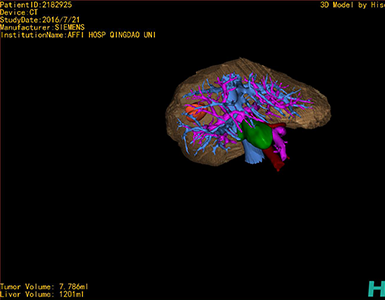

将0.625mm双源薄层CT资料的静脉期和动脉期Dicom格式文件导入海信CAS系统。

通过调节窗宽窗位调整CT序号,对肿瘤,肝实质,胆囊,下腔静脉,肿瘤,肝动脉、门静脉及肝静脉等进行三维重建;系统自动计算肿瘤体积和肝脏体积。

模拟手术操作,自动计算切除肿瘤体积。肝脏体积为1201ml,肿瘤体积为7.786ml,肿瘤体积为肝脏体积的0.6%,通过比对40-50岁正常肝脏体积为1368.38±279.24 ml,肝脏可先进行保守治疗,肾脏进行部分切除术。

术前手术方案的规划。

术前三维重建:

重建图片